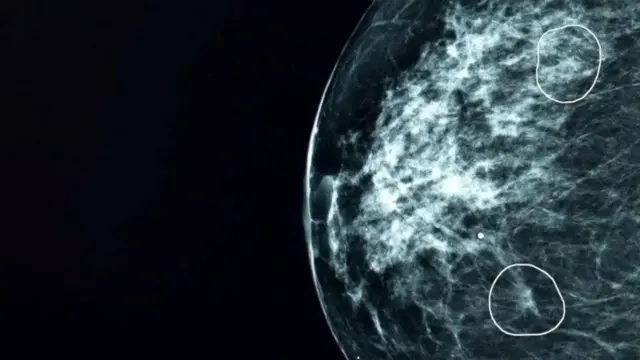

खेरॉन (Kheiron) या मेडिकल टेक्नालॉजी कंपनीने हे 'मिया' (Mia) नावाचे AI टूल बनवले आहे. मॅमोग्राम स्कॅनमध्ये कधीकधी अशा काही छोट्या आणि कठीण जागा असतात ज्या मानवी डोळ्यांना सहजासहजी दिसत नाहीत पण हे सॉफ्टवेअर त्या अचूकपणे शोधून काढते.

"जेव्हा मी दुसऱ्यांदा हॉस्पिटलमध्ये गेले तेव्हा डॉक्टरांनी सांगितले की AI मुळेच त्यांना काहीतरी संशयास्पद आढळले आहे. माझी पुन्हा तपासणी झाली आणि डॉक्टरांनी खात्री केली की AI ने दिलेला निकाल अगदी बरोबर होता. माझ्या शरीरात दुसऱ्या स्टेजचा (Grade 2) एक छोटासा ट्युमर होता जो इतका लहान होता की साध्या डोळ्यांना तो शोधणे अशक्य होते."